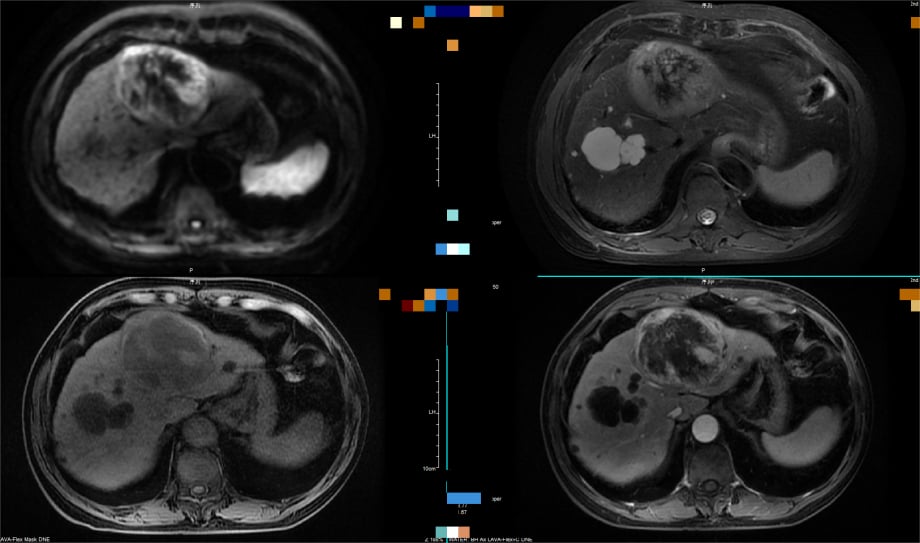

(图4)肝脏增强MRI提示:左肝巨块型病灶,弥散受限,T2WI混杂高信号,增强“快进快出”,诊断为肝癌。

(注:上图病例清晰展示了PET-CT(图3)对高分化肝癌诊断的局限性,而增强MRI(图4)则能根据典型的血流动力学特征做出明确诊断。)